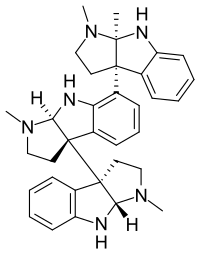

Indoles

- 18-Methoxycoronaridine

- 7-Acetoxymitragynine

- 7-Hydroxymitragynine

- ψ-Akuammigine

- Akuammidine

- Akuammine

- Coronaridine

- Eseroline

- Hodgkinsine

- Ibogaine

- Mitragynine

- Mitragynine pseudoindoxyl

- Noribogaine

- Pericine

- Pseudoakuammigine

Structures

| Indoles | ||||

|---|---|---|---|---|

|

7-Acetoxymitragynine |

|

Akuammidine |

|

|

|

-Mitragynine_Structural_Formula_V1.svg.png.webp)

|

|

|